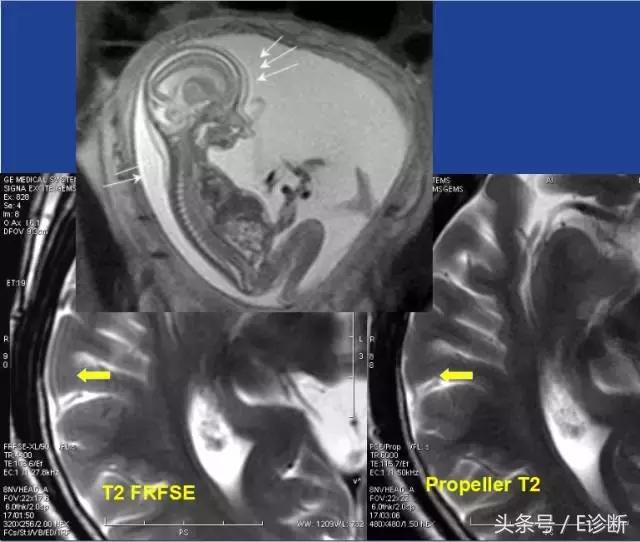

鬼影(Ghost)

原因:

回波中心偏移、持续相位编码偏移,或回波幅度不稳定。往往可由于系统不稳定或患者运动所致。

伪影特点:

往往出现在相位编码方向。由于患者运动的伪影只出现在运动的部位,而系统原因的伪影可在整个FOV中出现伪影。

运动伪影

由于病人(自主或不自主)运动(随机性的)或者血管的搏动性流动(周期性的)而造成的。

频率编码方向采集信号的采样时间明显短于一次相位编码的时间。伪影常出现在相位方向。

周期性运动:伪影出现在相位方向,等距地出现。伪影信号可高可低,取决于搏动结构相位相对于背景相位的关系(同相位则亮,反相位则暗)。